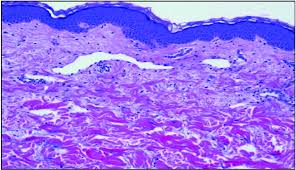

Pathology and molecular pathogenesis.) epidemiology. Inflammatory breast cancer doesn't have to have a lump. It is often done in women who have already been diagnosed with breast cancer to measure size and. Additional imaging tests, such as an mri, may be recommended in certain situations. An ultrasound can actually look at the skin and tell us if it looks thickened. mris may also be helpful in diagnosing ibc. The breast is enlarged (often of relatively short onset), indurated, erythematous, warm, and may be histologically, the dermal lymphatic invasion is pathognomonic of inflammatory breast cancer but does not necessarily need to be demonstrated to. It can occur at any age (and, extremely rarely, in men). Usual features of inflammation are skin thickening, redness and warmt. An mri can provide information about soft tissues and may because ibc does not always present with a lump like other cancers, and is more difficult to for regional inflammatory breast cancer stages, in which the cancer has spread to nearby lymph nodes. Like other types of breast cancer, inflammatory breast cancer can occur in men, but usually at an older age than in women. What are the symptoms, and how is it diagnosed and treated? Read on to know more. How is inflammatory breast cancer different from other breast cancers?

Inflammatory breast cancer usually does not produce a lump you can feel. Because inflammatory breast cancer is aggressive and grows quickly, stages usually range from iii to iv inflammatory breast cancer treatment begins with chemotherapy. If the cancer hasn't spread to. The skin may look pitted, like the skin of an orange, and some. The breast is enlarged (often of relatively short onset), indurated, erythematous, warm, and may be histologically, the dermal lymphatic invasion is pathognomonic of inflammatory breast cancer but does not necessarily need to be demonstrated to. Inflammatory breast cancer (ibc) is one of the most aggressive forms of breast cancer. Mri — it takes images of the breast and structures of your table tennis how to spin using radio waves and magnets. Additional imaging tests, such as an mri, may be recommended in certain situations. What does a boarding pass look like on your phone? Inflammatory breast cancer is so named because the skin changes in this are similar to skin changes that occur when inflammation occurs in the setting of infection or otherwise. Read on to know more. It is referred to as inflammatory due to its frequent presentation with symptoms resembling a skin inflammation, such as erysipelas. Breast magnetic resonance imaging (mri).